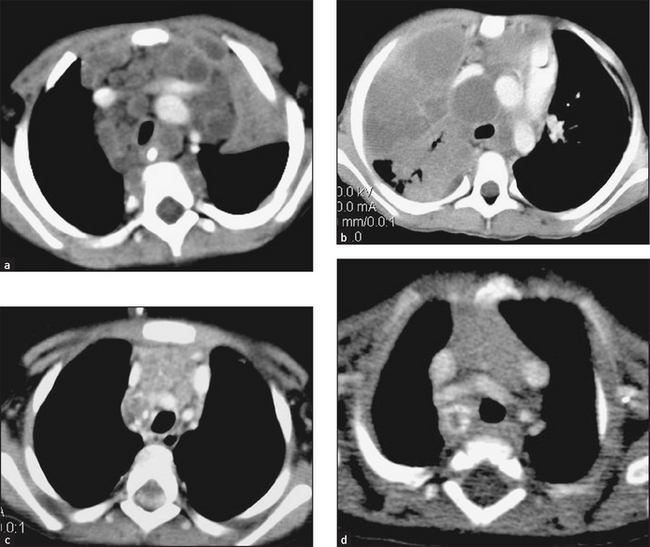

CT and ultrasound are often used to help determine the presence of splenomegaly or lymphadenopathy (see Figures 22.16 and 22.17).